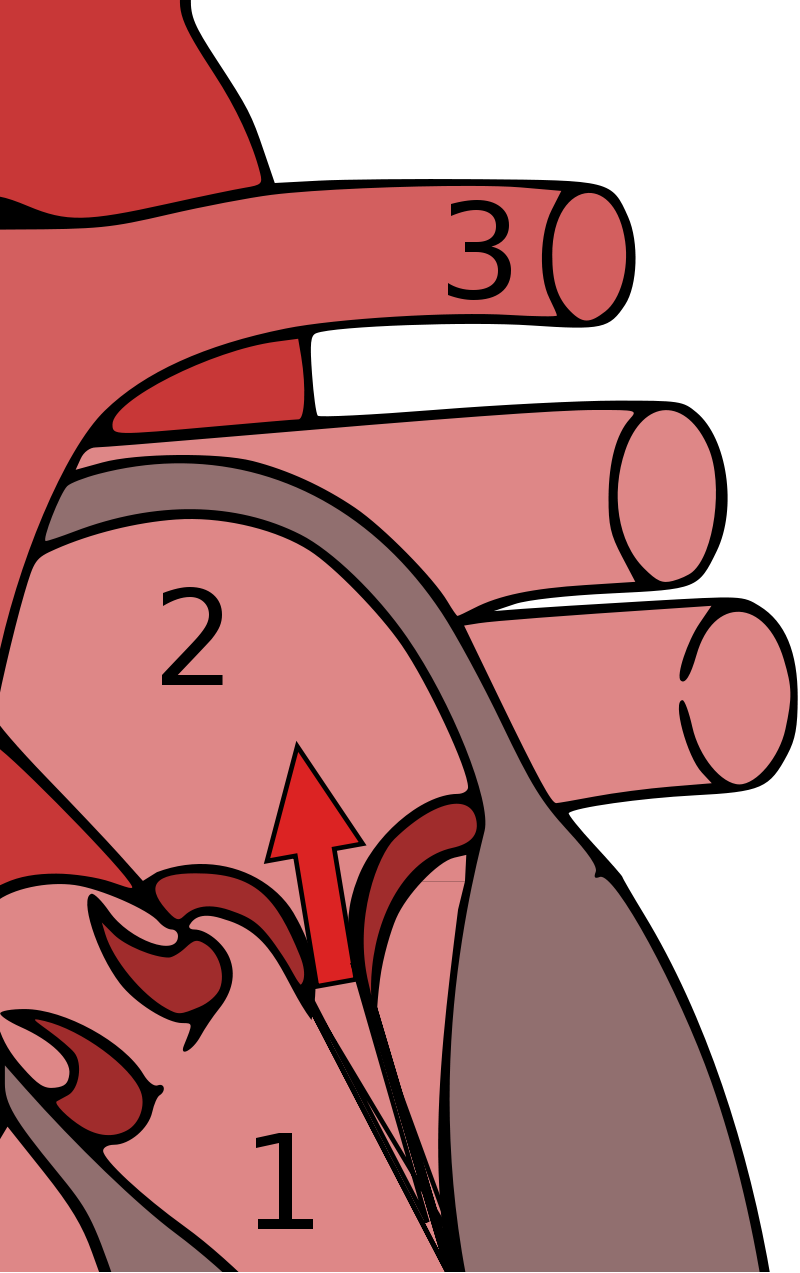

Aortic Regurgitation

Aortic regurgitation is the backflow of blood from the aorta into the left ventricle during diastole caused by aortic root dilatation or valve damage.

Aortic regurgitation is the most common cause of isolated aortic root dilation.

Clinical features of aortic regurgitation include an early, blowing diastolic murmur and hyperdynamic circulation due to increased pulse pressure.

The difference between systolic and diastolic pressures is known as pulse pressure.

Diastolic pressure decreases as a result of regurgitation, but systolic pressure increases as a result of increased stroke volume.

The increased pulse pressure associated with aortic regurgitation is characterized by:

- Water-hammer pulse

- Pulsating nail bed also known as the Quincke pulse

- Head bobbing

Aortic regurgitation results in left ventricle dilation and eccentric hypertrophy due to volume overload.

Treatment of aortic regurgitation is valve replacement once left ventricle dysfunction develops.